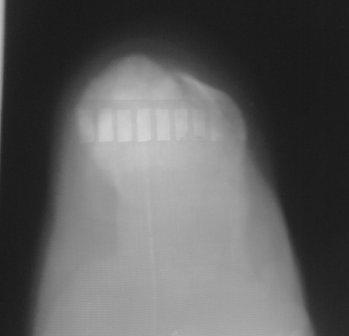

Здравствуйте, уважаемые коллеги. Обратился больной 29лет, через 25 дней после травмы с переломом обеих пяточных костей, слева без смещения, справа внесуставной отрывной перелом бугра пяточной кости (утиный клюв) в гипсовой повязке.

Р-снимки не качественные, снял на моб. на улице, поэтому прошу прошения!